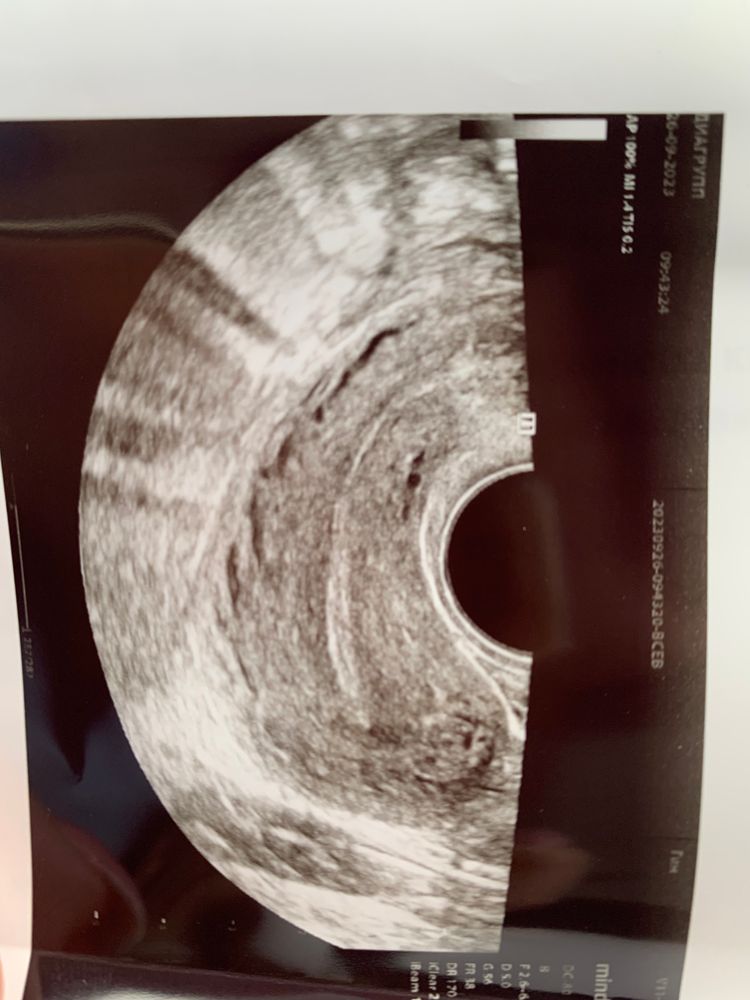

С 14 по 22 у вас ХГЧ вырос всего на 58 единиц (152). А должен быть уже 1600 не меньше. Биохимическая беременность это, а из за поддержки удерживаете месячные. Отменять все надо и ждать начало цикла. Если я правильно понимаю, это точка не в матке, а с её краю. А белая полоса посередине это как раз полость матки сомкнутая.

Если матка соответствует 5 неделе, то скорее все это бб, либо внематочная, раз не видят в матке, а хгч растёт..